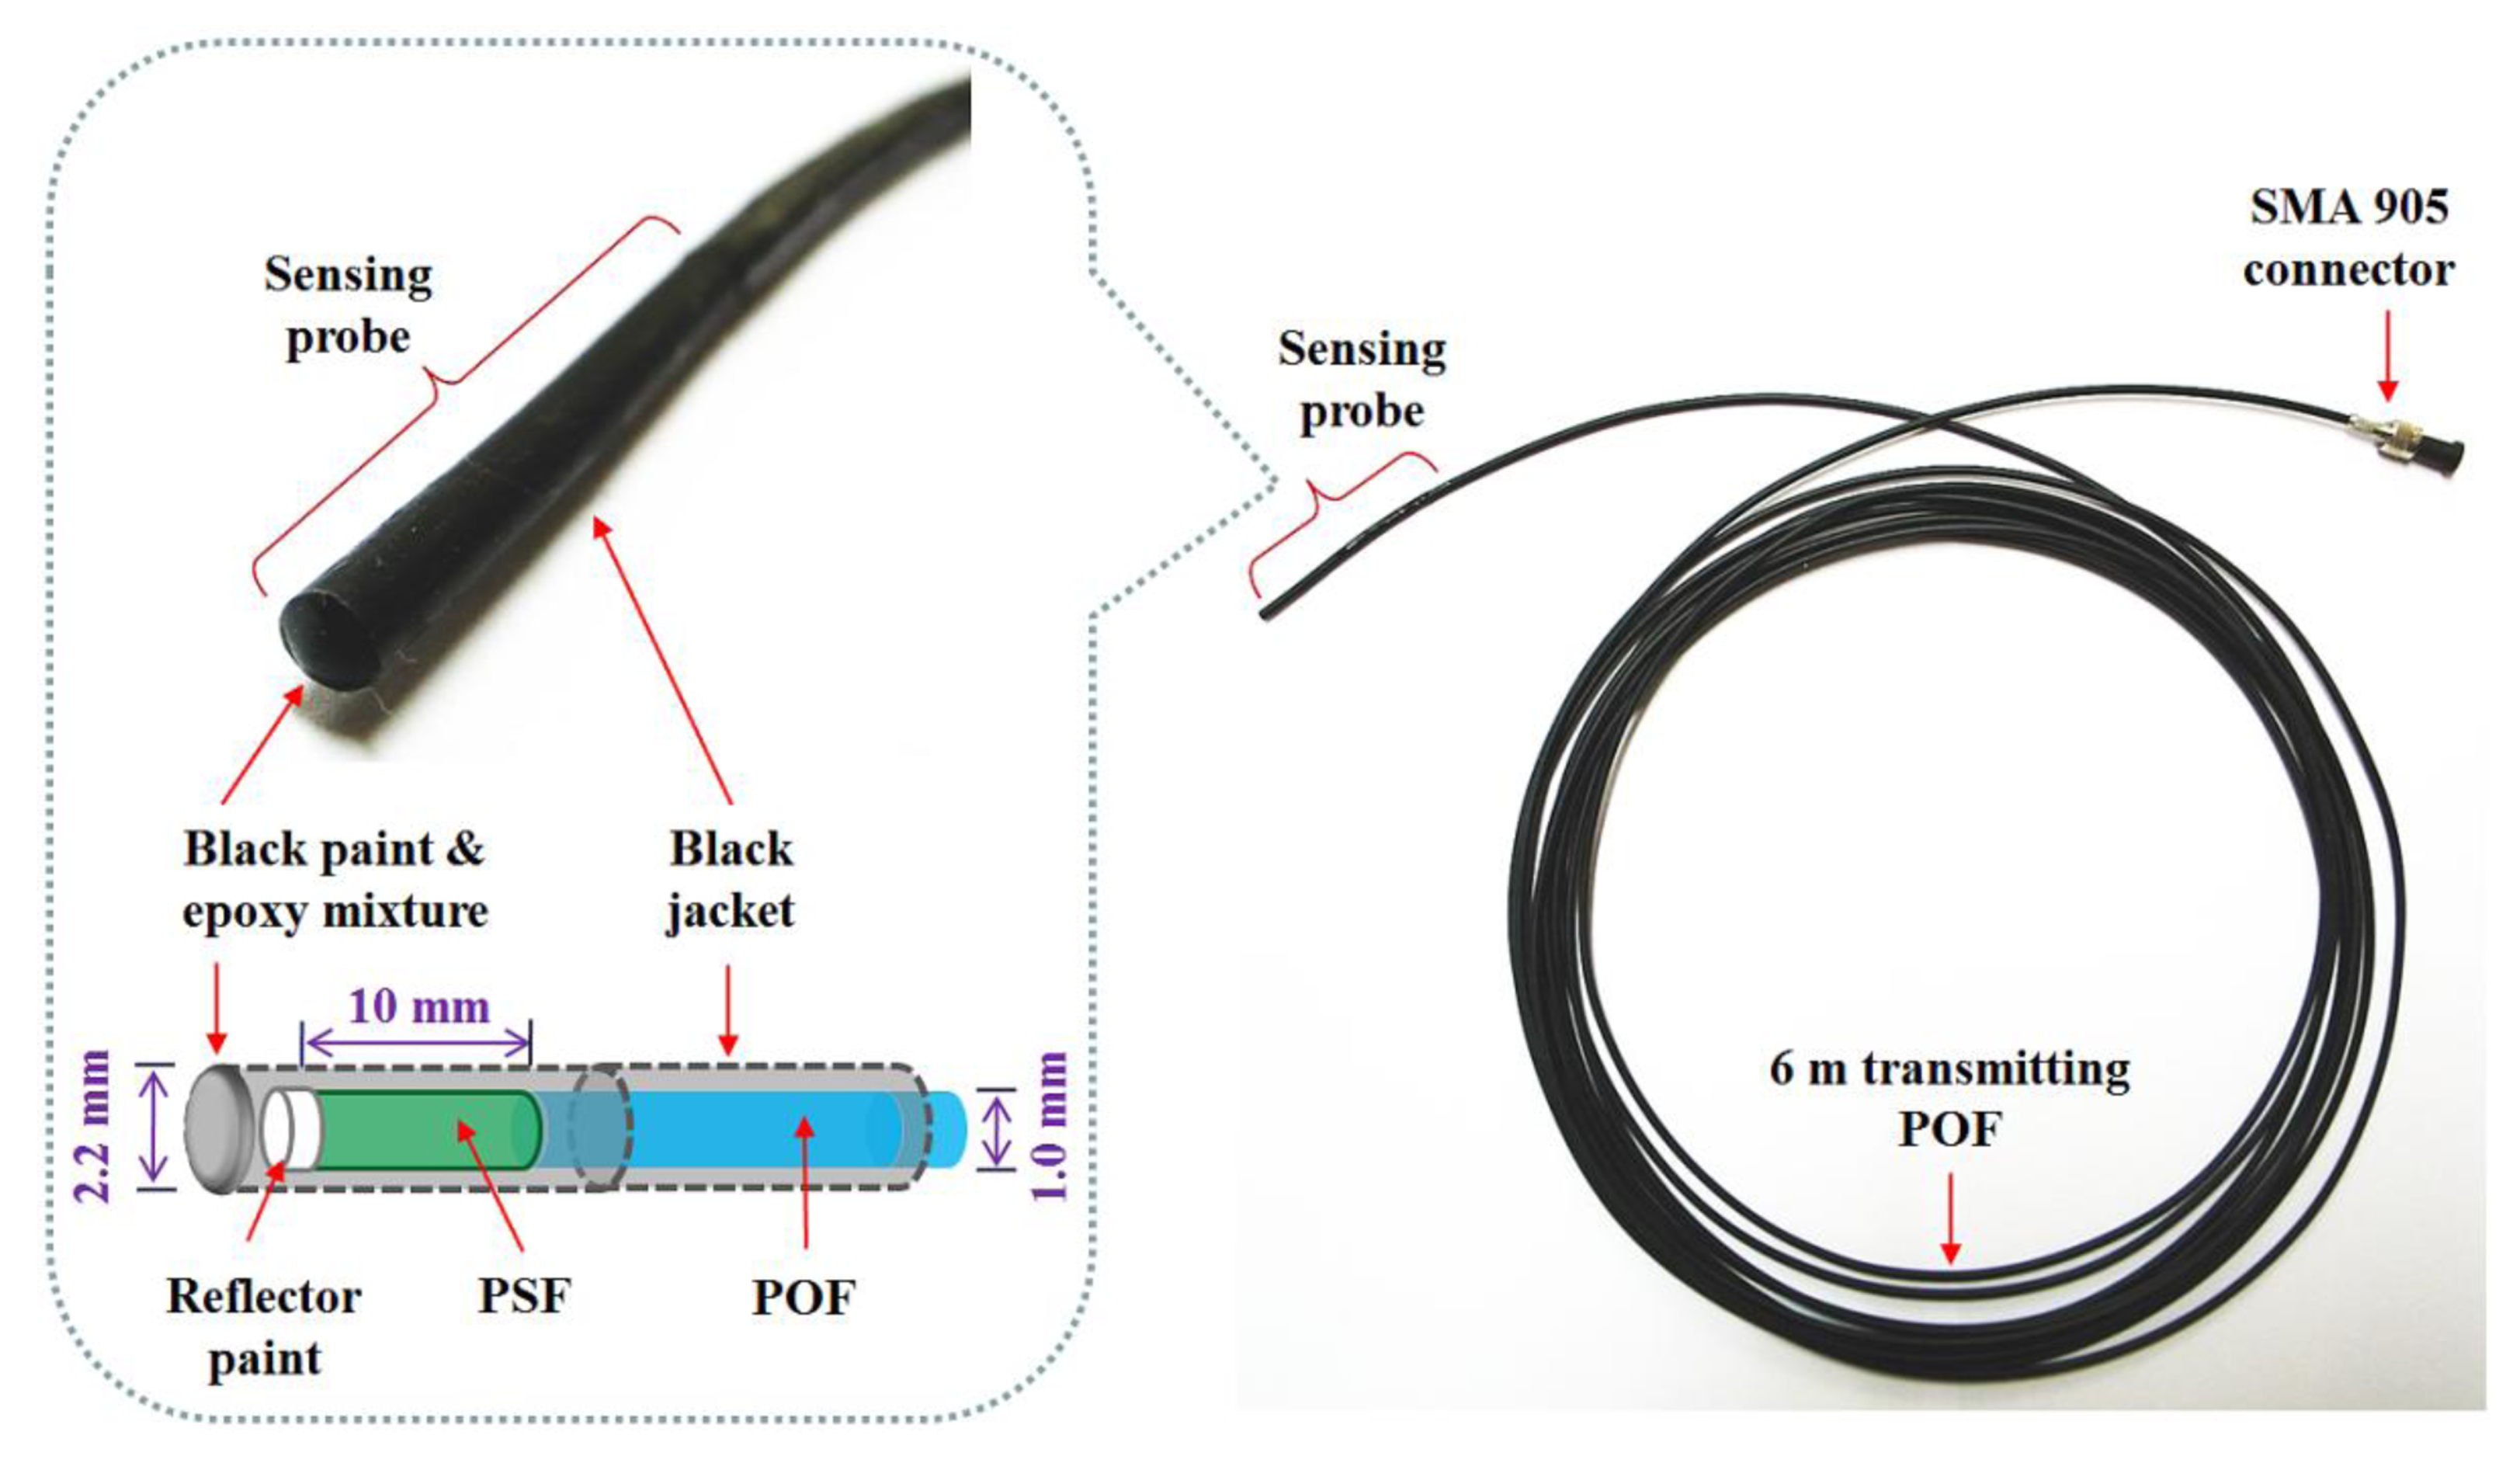

2.1. Fabrication of a Sensing Probe

To produce scintillating light having dose information, as an organic scintillator, a PSF (BCF-12, Saint-Gobain Ceramic & Plastics, Hiram, OH, USA) was used. The PSF has a cylindrical shape and a core/clad structure with an outer diameter of 1 mm. The refractive indices of the core and the cladding are 1.60 and 1.49, respectively, and the numerical aperture (NA) is 0.58. The core is synthesized with polystyrene (PS) and fluorescent dopants and the cladding material is polymethylmethacrylate (PMMA). The emission peak wavelength and the decay time of the PSF are 435 nm and 2.7 ns, respectively.

A multimode POF (GH-4001, Mitsubishi Rayon, Tokyo, Japan) with a step refractive index profile is used to transmit the scintillating light from the PSF to a photon-counting device, a MPPC (S10362-11-100U, Hamamatsu Photonics, Hamamatsu, Japan) with an active area of 1 × 1 mm2. The diameter of the core is 0.98 mm and the outer diameter of the POF is equal to that of the PSF. The core is made of PMMA resin with a refractive index of 1.49 and the fluorinated polymer based cladding has a refractive index of 1.402; thereby the NA of this POF is 0.5. The POF is covered by a black polyethylene (PE) jacket with an outer diameter of 2.2 mm to shield light noise and to protect the POF from ambient contamination.

Figure 1 shows a photograph of the completed sensing probe and its internal structure. To maximize the amount of scintillating light reaching the MPPC, both ends of the PSF and POF, respectively, were polished with various types of lapping films in a regular sequence. The bared PSF with a length of 10 mm was connected to the distal end of the jacketed POF with a length of 6 m and then the uncoupled end of the PSF was coated with a titanium dioxide (TiO2)-based reflector paint (BC-620, Saint-Gobain Ceramic & Plastics) to increase the collection efficiency of the scintillating light. Furthermore, the outer surface of the PSF was covered with a black PE jacket and the distal end was coated by a mixture of black paint and an optical epoxy to block external light. Finally, a subminiature type A (SMA) 905 connector was installed at the opposite end of the POF to enable the sensing probe to be connected with the MPPC.